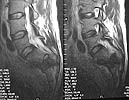

A 28 year old male jumped from the 4th floor on 11-25-2000 sustaining an L1 burst fracture that has been fixed anteriorly by the neurosurgeon with a strut between T12 and L2. A Kaneda device was placed anteriorly as well. My concern is the pelvic ring injury. There are bilateral sacral fractures through the foramen and a transverse element through the sacrum between S2 and S3. the lower part of the sacrum is displaced forward. Anteriorly there are right superior and inferior pubic rami fractures.

MR1

MR2